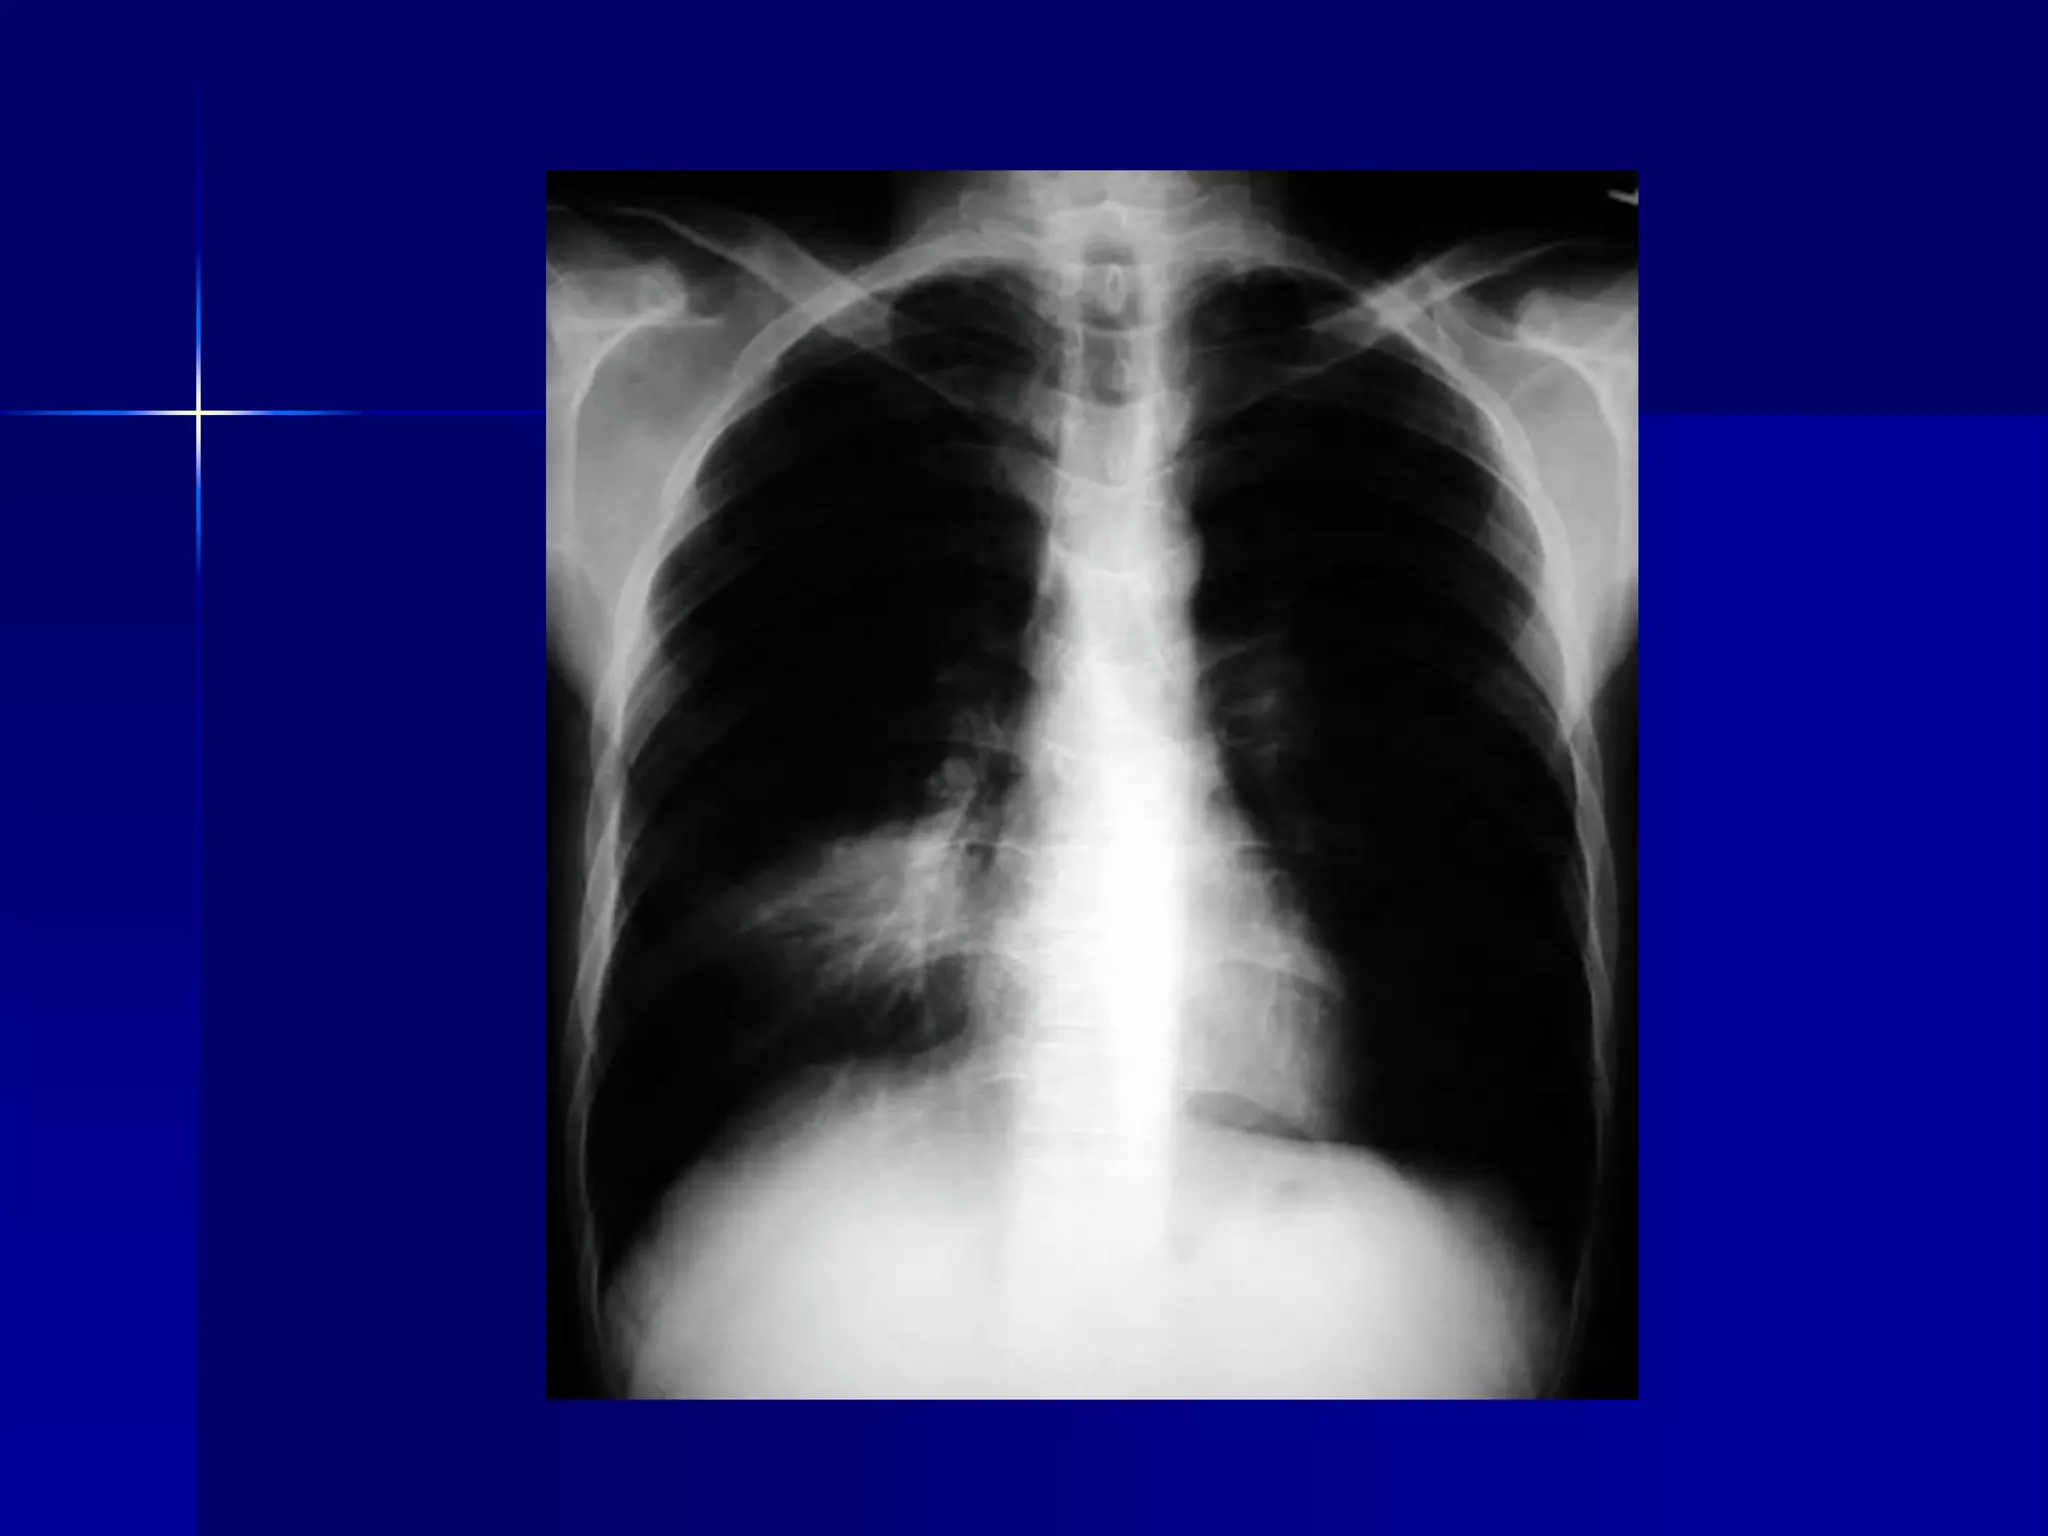

Atelectasis Left Lung

 Homogenous density left hemithorax

 Mediastinal shift to the left

 Diaphragmatic and heart silhouette

are not identifiable